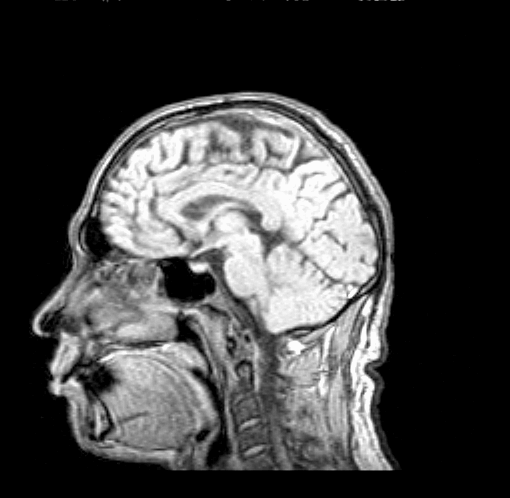

Это конфигурация для работы с изображениями. На рисунке видны два главных окна системы: окно Управление (справа) и окно Изображения, с изображением среза, полученного на рентгеновском томографе.